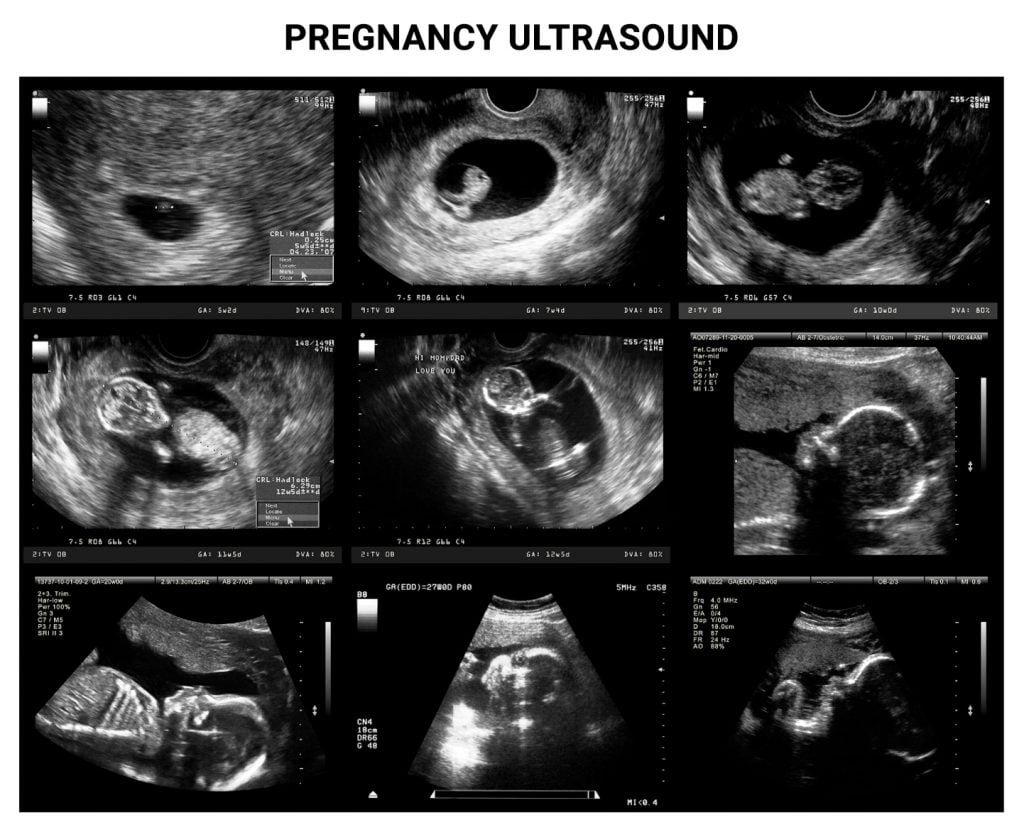

How To Read A Fetal Sonogram . Recognize the ultrasonographic findings of pregnancy pathologies. While pregnancy ultrasounds are a reliable way to track and measure your baby’s progress, reviewing your ultrasound report can be daunting. decoding and interpreting ultrasound abbreviations is essential for understanding various aspects of the pregnancy,. fetal ultrasounds are a standard prenatal screening tool and medical imaging test used to monitor your health and the health of your baby during pregnancy. the measurements noted with a “cm” (centimeters) or “mm” (millimeters) are usually fetal measurements. learn how to read an ultrasound picture in conjunction with your radiology report. Technicians will measure the size of the fetus at each ultrasound as they grow to look for abnormalities and possible chromosomal markers that indicate down syndrome and trisomy disorders. these ultrasounds are often advertised as a way for families to create keepsake images or to learn the sex of a. after reading this post, you will learn how to use basic obstetrical ultrasound to do the following: this activity reviews the classifications and indications of fetal ultrasounds in each trimester and highlights the role of the.

Technicians will measure the size of the fetus at each ultrasound as they grow to look for abnormalities and possible chromosomal markers that indicate down syndrome and trisomy disorders. learn how to read an ultrasound picture in conjunction with your radiology report. these ultrasounds are often advertised as a way for families to create keepsake images or to learn the sex of a. fetal ultrasounds are a standard prenatal screening tool and medical imaging test used to monitor your health and the health of your baby during pregnancy. While pregnancy ultrasounds are a reliable way to track and measure your baby’s progress, reviewing your ultrasound report can be daunting. after reading this post, you will learn how to use basic obstetrical ultrasound to do the following: Recognize the ultrasonographic findings of pregnancy pathologies. decoding and interpreting ultrasound abbreviations is essential for understanding various aspects of the pregnancy,. the measurements noted with a “cm” (centimeters) or “mm” (millimeters) are usually fetal measurements. this activity reviews the classifications and indications of fetal ultrasounds in each trimester and highlights the role of the.